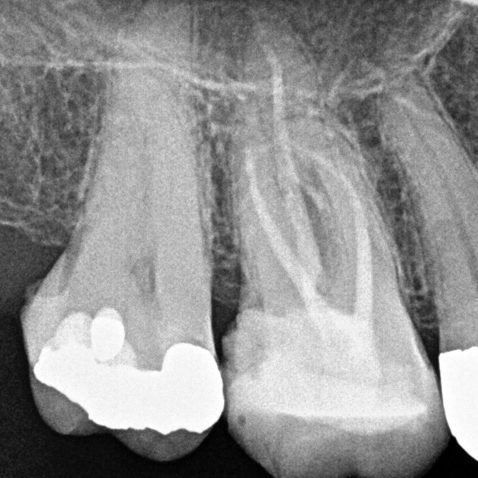

Figure 1: MB1 and MB2 are two separate canals.

- Preoperative radiograph

- Mid-fill radiograph showing MB1 and MB2 are completely separate canals with individual apical foramen; both canals have acute apical curvatures

- Postoperative radiograph; a lateral canal was noted in the palatal canal.